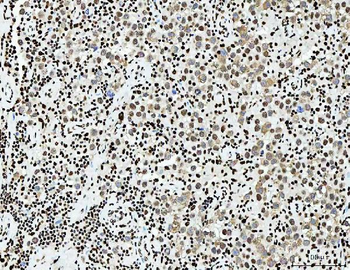

10 μg, 100 μgAnti-PC4/SUB1 Antibody (monoclonal, 6B5B10) [orb1145777]

IHC, WB

Human, Mouse, Rat

Mouse

Monoclonal

Unconjugated